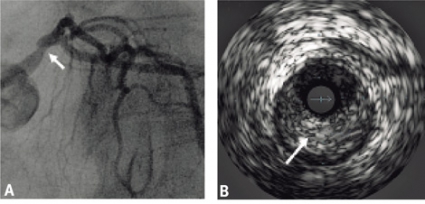

Ytterligare utvärdering av LMS och proximala LAD med intrakoronar tryckmätning och bestämning av »fractional flow reserve« (FFR) under adenosinprovokation samt intravaskulärt ultraljud utfördes. FFR distalt om LMS och LAD var 0,89, vilket hemodynamiskt motsvarar en icke-signifikant stenosering. Undersökning med intravaskulärt ultraljd visade påtagliga ateromatösa förändringar i LMS med en sannolikt signifikant stenos, där minsta diametern var 2,6 mm, minsta arean 4,7 mm2 och areastenosen 75 procent. Det förelåg inga tecken till akut koronar patologi såsom plackruptur, fyllnadsdefekter eller trombos i LMS eller i proximala LAD (Figur 4 A och B). Ekokardiografisk undersökning verifierade ballonering av den apikala hälften av vänsterkammaren.